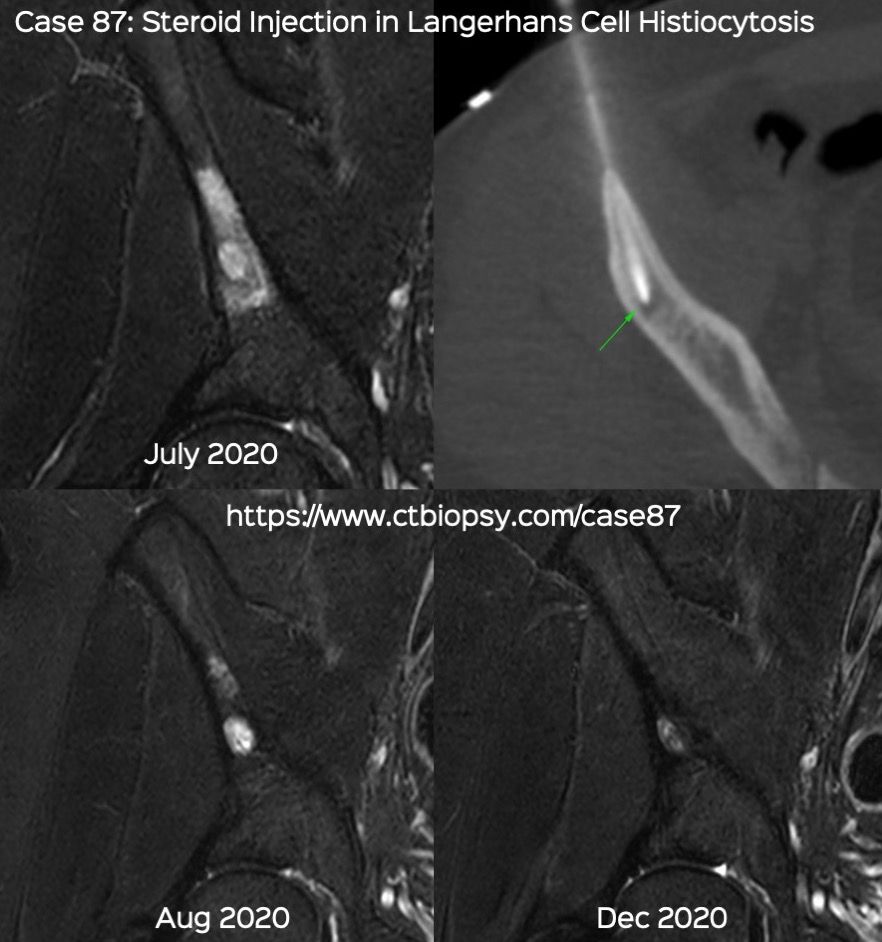

Case 87: Intra-Lesional Steroid Injection in Langerhans Cell Histiocytosis